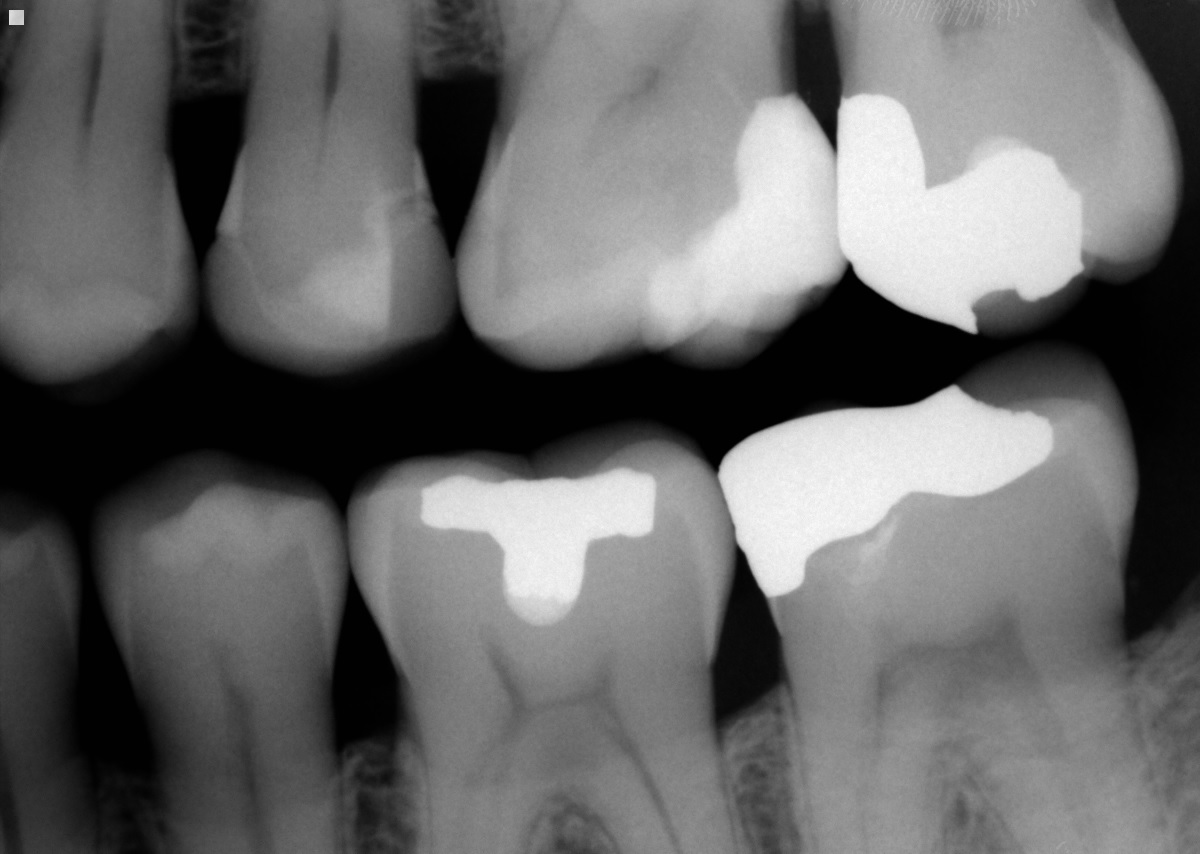

Lower left premolar with fractured amalgam, lingual cusp and wall, and Fractured Cusp Back Molar You may have a fractured cusp if a crack forms around a dental filling. a cracked molar is a common type of tooth fracture, and it is usually unexpected. It often comes with some pain and discomfort. how is a broken molar treated? Teeth that are broken beneath the gum line are known as subgingival fractures. Each tooth. Fractured Cusp Back Molar.